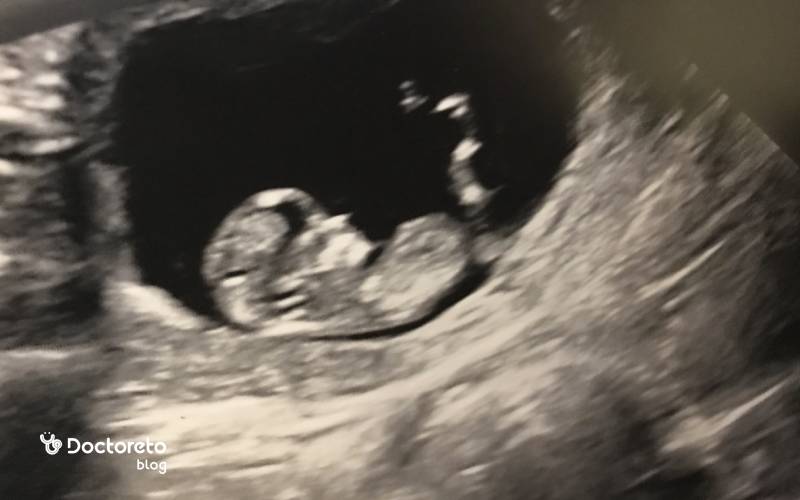

در هفته یازدهم بارداری، سونوگرافی نقش مهمی در تأیید سلامت جنین و محاسبه دقیق سن بارداری دارد. اندازهگیری طول سری تا نشیمن (CRL) و بررسی شفافیت نوک گردن (NT) در این سونوگرافی برای ارزیابی اختلالات کروموزومی ضروری است. سونوگرافی در این هفته نشاندهندهٔ شکلگیری بیشتر اعضای بدن جنین است: صورت و اندامها واضحتر میشوند و حرکتهای ظریف در سونوگرافی مشاهده میشود. در این مرحله، جنین در سونوگرافی حدود ۴–۵ سانتیمتر طول دارد و ضربان قلب آن به وضوح شنیده میشود.

همچنین بهترین زمان برای سونوگرافی nt تی در هفته ۱۱ بارداری تا ۱۳ هفته و ۶ روز است. درصورتیکه تصویر سونوگرافی واضح نباشد، ممکن است پزشک از شما بخواهد که وضعیت خود را تغییر دهید یا سونوگرافی را دوباره انجام دهید. در سونوگرافی میتوان حرکات جنین را بررسی کرد. اگر دوقلو باردار باشید، در این مرحله سونوگرافی، بندناف جنینها و یک یا دو جفت را نشان میدهد. در سونوگرافی میتوانید ضربان قلب جنین را بشنوید.

در جنین ۱۱ هفتهای، نسبت سر به بدن هنوز بزرگتر است اما گردن مشخصتر شده و بدن از حالت خمیده ابتدایی خارج میشود. انگشتها و انگشتان پا از هم جدا شدهاند، مفاصل زانو و آرنج فعالترند و جوانههای دندانی اولیه شکل گرفتهاند. کبد هنوز نقش پررنگی در خونسازی دارد و رودهها که تا همین حوالی در بند ناف بودند، بهتدریج به داخل شکم برمیگردند. شکل جنین در هفته یازدهم بارداری در سونوگرافی با ستون فقرات روشن و حرکات جهشی کوتاه قابلمشاهده است.